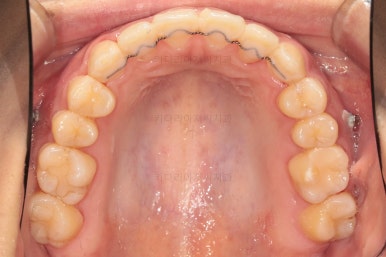

치열의 고른 느낌 좋고요.

덧니, 교합, 중앙선 등 모든게 좋아졌네요.

부산치아교정치과 전후 비교해 보겠습니다.

교합, 맞물림, 중앙선, 덧니, 입매, 앞니위치 및 각도 모든게 잘 마무리 되었습니다.